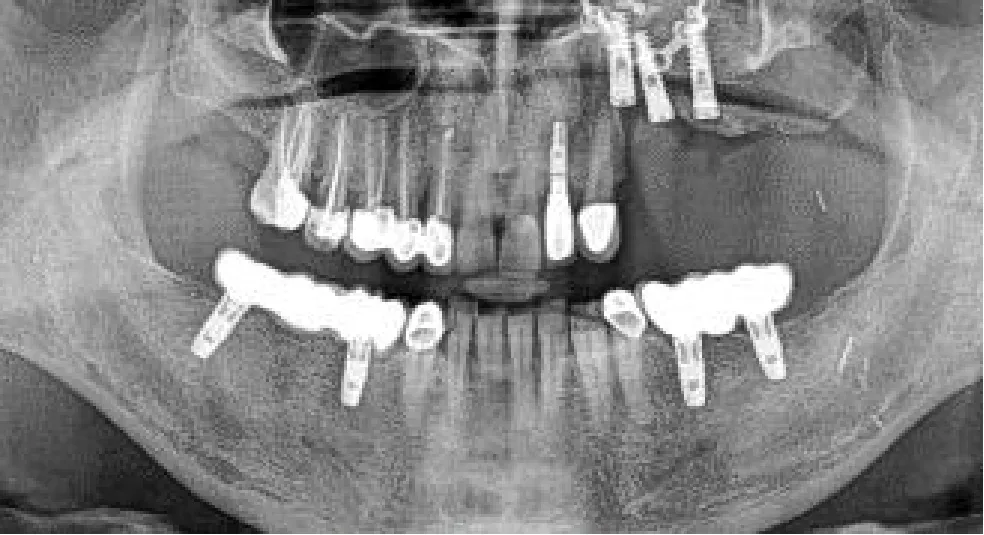

We placed a total of 56 implants, 25 in the upper jaw, and 31 in the lower jaw. 18 implants were inserted into the fibula bone (conventional or double barrel), 6 into the iliac crest, and 32 in the patient remnant bone; 15 implants were placed in irradiated bone (1 fibula and the ALT with vastus lateralis case).

In those eleven patients, we treated 14 jaws, 3 jaws exclusively with sCAIS (closed transmucosal technique, 13 implants), 4 jaws with dCAIS (13 implants), and the other 7 with a combination of both methods (30 implants). In those 11 navigated jaws, we opened a flap for proper bone visualization and soft tissue remodeling. Adequate bone width control is advisable in extremely narrow alveolar bone cases. Vestibular cortical plate fenestration was noticed in three implants, so we extracted the implants and placed them again in different locations. Those three freehand implants were visually oriented and placed in the best-quality bone that was found available intraoperatively without considering the virtual planning. That is why they were withdrawn from the statistical analysis. We also withdrew our third patient (3 implants) from the analysis, since we did not achieve enough stability of the optical markers. Hence, the navigation procedure was not accurate enough, ending the surgery in a conventional non-guided freehand method. Consequently, the implants were placed with an eye-oriented insertion axis and without considering the prosthetically driven surgical planning. Despite the intraoperative complication, the osseointegration was uneventful in the fibula and we ended with the planned fixed screw-retained prosthesis (Table 1, patient 5, orthopantomogram with the prosthesis in place). Therefore, we withdrew a total of 6 freehand placed implants from our data analysis

All implants except one achieved a successful osseointegration measured during follow-up by ISQ stability (frequency of resonance), resulting in a 98% osseointegration success rate. This follow-up is, however, too short to extract conclusions.

Nevertheless, our first four cases were splintless dynamic-guided surgeries (one iliac crest, one fibula double barrel, and two conventional fibula flaps). We applied the tooth-supported silicone jig dCAIS concept for patient registration, which was the most inaccurate method (linear crestal insertion error 2.7 mm, apical deviation 3.94 mm, and 10° of angular mismatch). These values are similar to those reported in the literature for conventional freehand non-guided placement in simple non-oncological cases. Vercruyssen et al. (35) revealed a crestal error of 2.7 mm, an apical error of 2.9 mm, and an angular deviation of 9.9°. For the same features, Block et al. (36) reported 1.67 mm, 2.51 mm, and 7.69°, respectively. In our study, the tooth-supported silicone jig provided an adequate registration. However, it resulted unstable during surgery. Consequently, the cases with large anatomical distortion (fibula cases patients 3 and 4 with a basal fibula bone placement and a thick skin paddle) showed the lowest accuracy. Moreover, we had to stop the navigation procedure in the third patient and continue with a conventional freehand method. Despite the mismatch, osseointegration was uneventful and the initial group of four patients ended with adequate screw-retained implant-supported prosthesis.